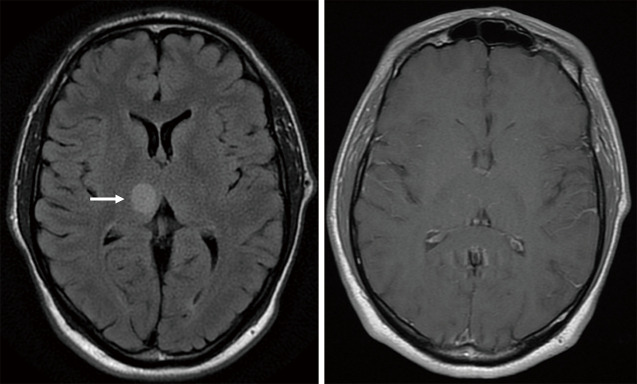

Abstract Image